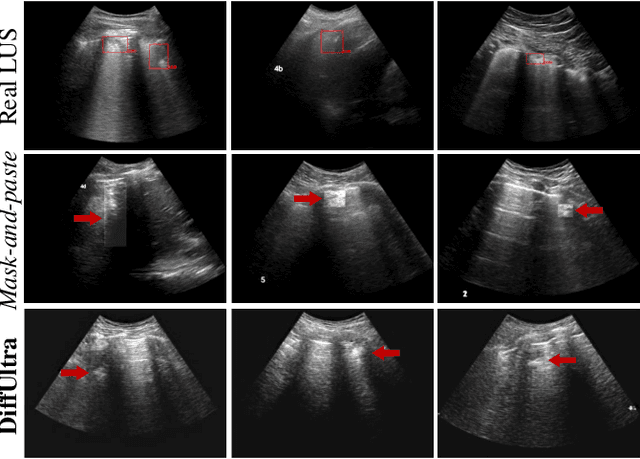

Abstract:Developing reliable healthcare AI models requires training with representative and diverse data. In imbalanced datasets, model performance tends to plateau on the more prevalent classes while remaining low on less common cases. To overcome this limitation, we propose DiffUltra, the first generative AI technique capable of synthesizing realistic Lung Ultrasound (LUS) images with extensive lesion variability. Specifically, we condition the generative AI by the introduced Lesion-anatomy Bank, which captures the lesion's structural and positional properties from real patient data to guide the image synthesis.We demonstrate that DiffUltra improves consolidation detection by 5.6% in AP compared to the models trained solely on real patient data. More importantly, DiffUltra increases data diversity and prevalence of rare cases, leading to a 25% AP improvement in detecting rare instances such as large lung consolidations, which make up only 10% of the dataset.